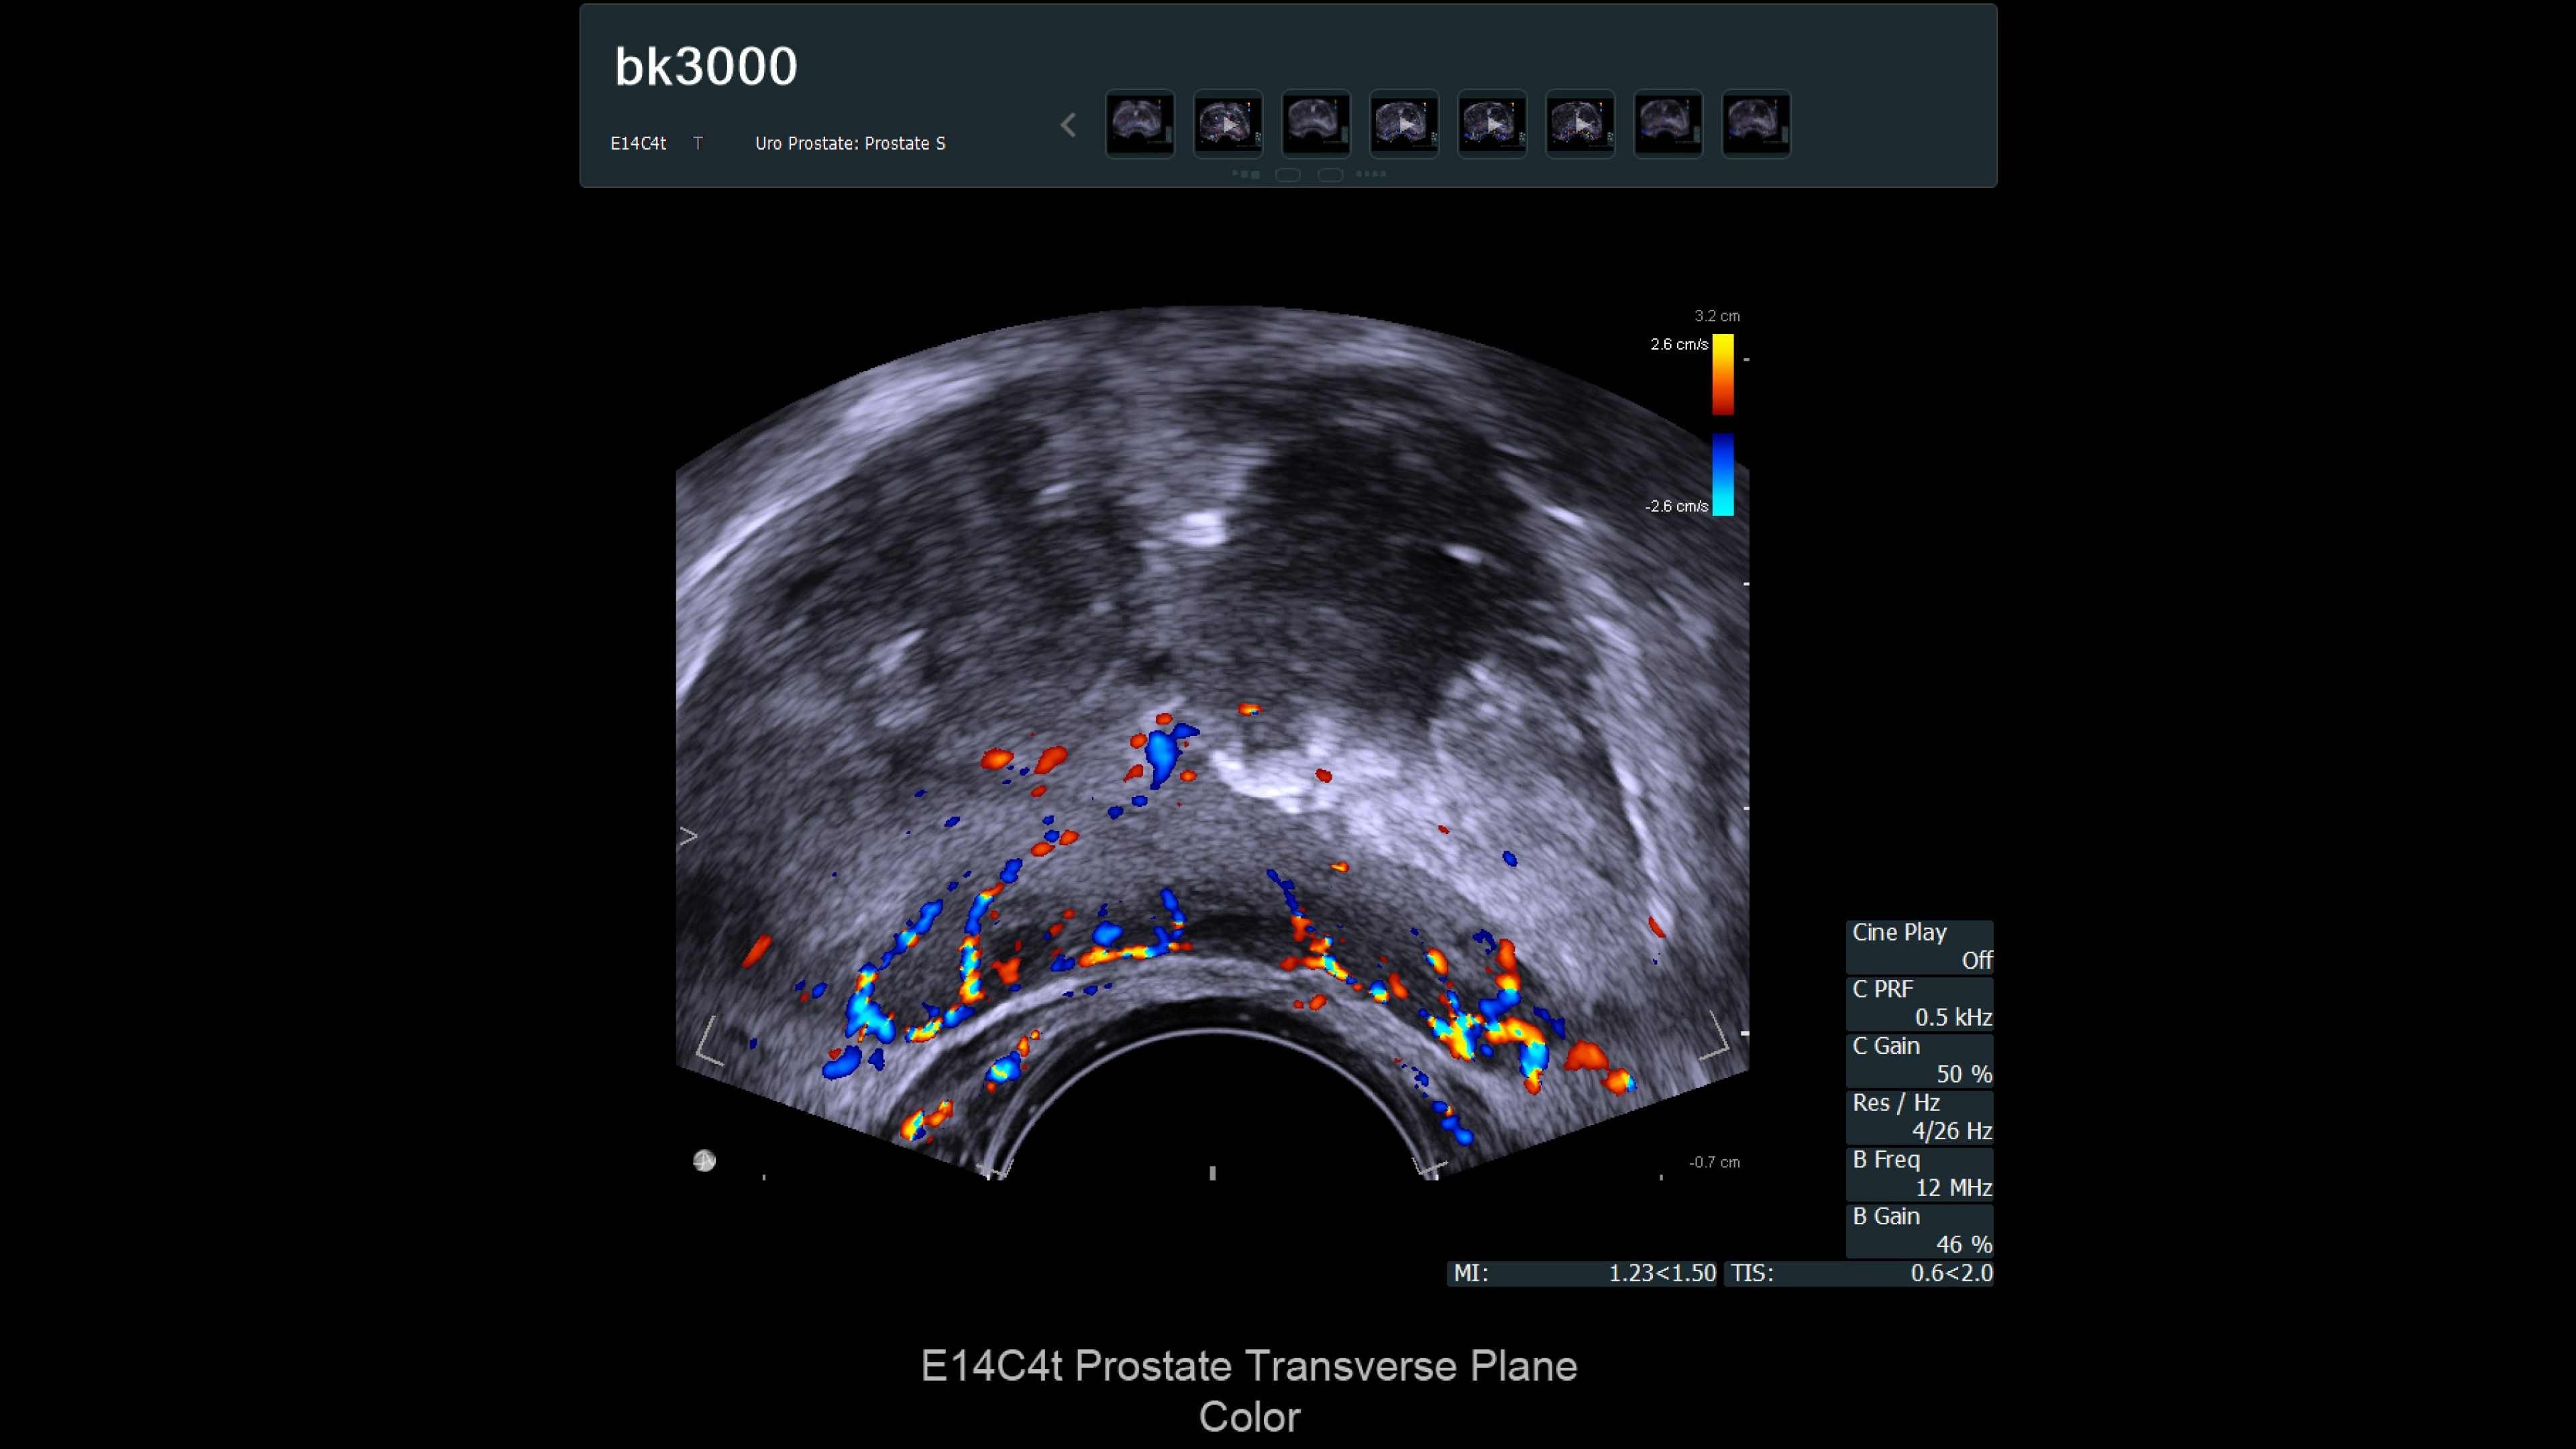

Ultra high-resolution imaging for Urology

The bk3000 ultrasound machine offers ultra high-resolution imaging for urology, including exceptional prostate, kidney, bladder, and testes imaging. It features real-time, high-definition prostate images, elastography for targeted biopsies, and a unique Triplane transducer for simultaneous biplane and endfire imaging. The system enhances lesion targeting with fusion-guided biopsies, combining MRI and ultrasound for precision prostate biopsies. Advanced imaging features and dedicated transducers improve visualization and treatment confidence during prostate interventions.